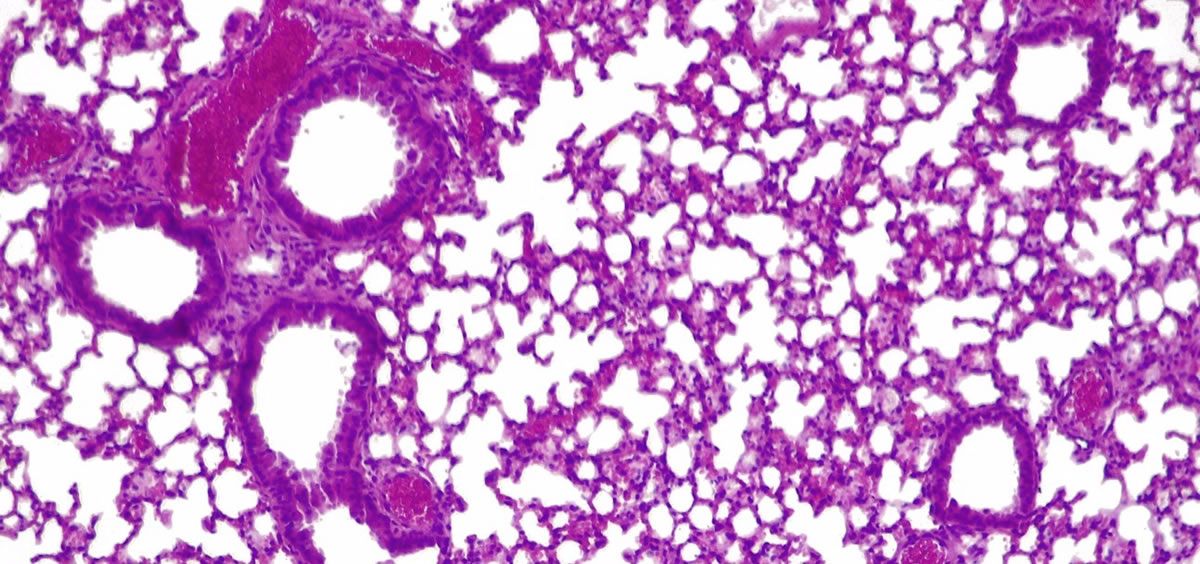

Las infecciones causadas por 'presudomonas aerugionosa' son difíciles de tratar porque la bacteria vive en comunidades que forman biopelículas, que pueden adherirse a varias superficies del cuerpo, formando estructuras impenetrables que escapan al alcance de los antibióticos.

Las biopelículas de esta bacteria crecen en la superficie de los tubos endotraqueales utilizados por pacientes en estado crítico quienes, por lo tanto, requieren ventiladores mecánicos para respirar.

Esto causaneumonía asociada al ventilador (NAV), una afección que afecta hasta uno de cada cuatro (9-27%) pacientes que requieren intubación, y la incidencia supera el 50% en el caso de los pacientes intubados por Covid-19 grave.

Para probar su eficacia, recogieron biopelículas de 'presudomonas aerugionosa' de los tubos endotraqueales de pacientes en unidades de cuidados intensivos, y mostraron que el tratamiento atraviesa la barrera y disuelve con éxito las biopelículas.